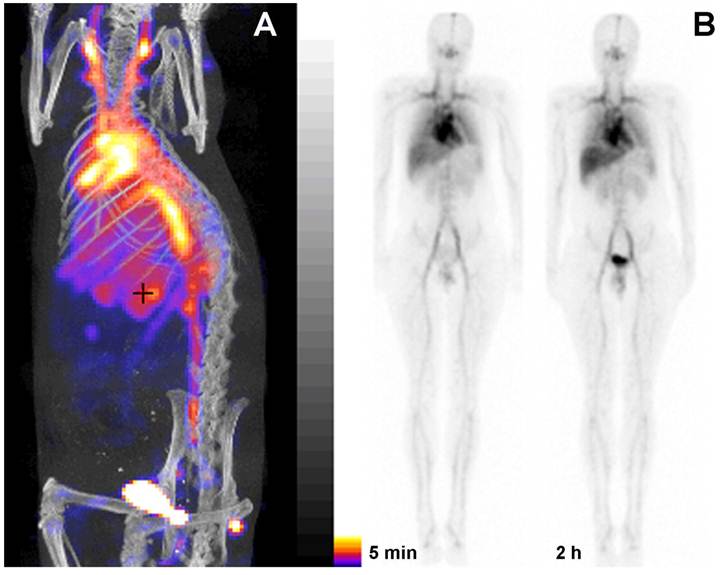

Figure 5

PGC as a blood pool imaging agent. A- a fusion SPECT/CT image of a rat 30 min after the injection of 99mTc-labeled PGC (2 mg PGC-DTPA/kg, 1 mCi 99mTc/rat). The image was obtained using NanoSPECT/CT (Bioscan Inc.); B- an image obtained in a healthy volunteer during Phase I clinical trials. Serial anterior whole-body images are shown taken immediately (30 min) and 2 h after the injection of 25 µg PGC-[99mTc]DTPA/kg (total dose - 20 mCi 99mTc). Note the distribution in the blood pool and low uptake in the lung, spleen and liver. Adapted from [38].

To obtain a labeling kit, we combined PGC-DTPA with a buffering solution in the presence of Sn(II) to enable reductive conversion of pertechnetate to a Tc oxocomplex [37]. After testing the kit in vitro and in three animal species [37] (representative SPECT/CT image in rats Fig. 5A) we tested PGC-DTPA[99mTc] in a phase I clinical trail that showed promising results. Twenty mCi (70 MBq) of the compound were injected I.V. and serial anterior and posterior whole body images were collected immediately and after a delay [38] (Fig. 5B). The compound showed the expected distribution and the heart and major blood vessels were clearly distinguishable up to 24 h post injection. The blood half life of the compound was 20.6 ± 2.3 hr. In four of the volunteers 22.1% ± 2.5% of the compound had been excreted through the kidneys 24 hr after iv administration, while the other two volunteers showed a greater distribution of the agent to the liver and spleen presumably due to DTPA labeling instability and not due to immunogenicity. A combination of the PGC long blood half-life with the advantages of a simple labeling protocol make this synthetic copolymer kit a potential substitute for blood products in blood pool imaging under the conditions when other blood pool imaging modalities fail to produce adequate results.